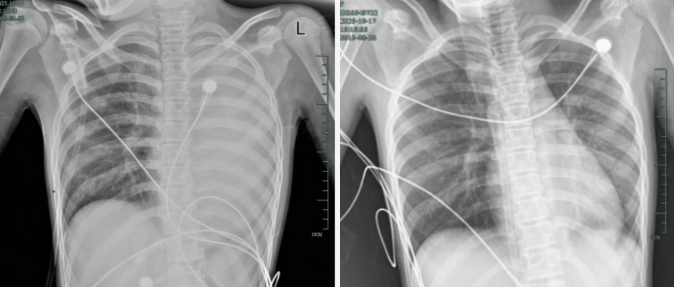

治療前後影像對比,左肺從“白肺”到正常狀態。

據介紹,笑笑一開始只是輕微咳嗽,發熱到38℃,檢查提示肺炎、肺不張,轉診到浙大四院兒科時,病情已經急劇惡化,出現呼吸急促、胸悶胸痛,體溫38.5℃,只能靠5L/min的面罩吸氧維持血氧,胸片顯示左肺已完全呈 “白肺” 改變,肺部炎症進展迅猛。